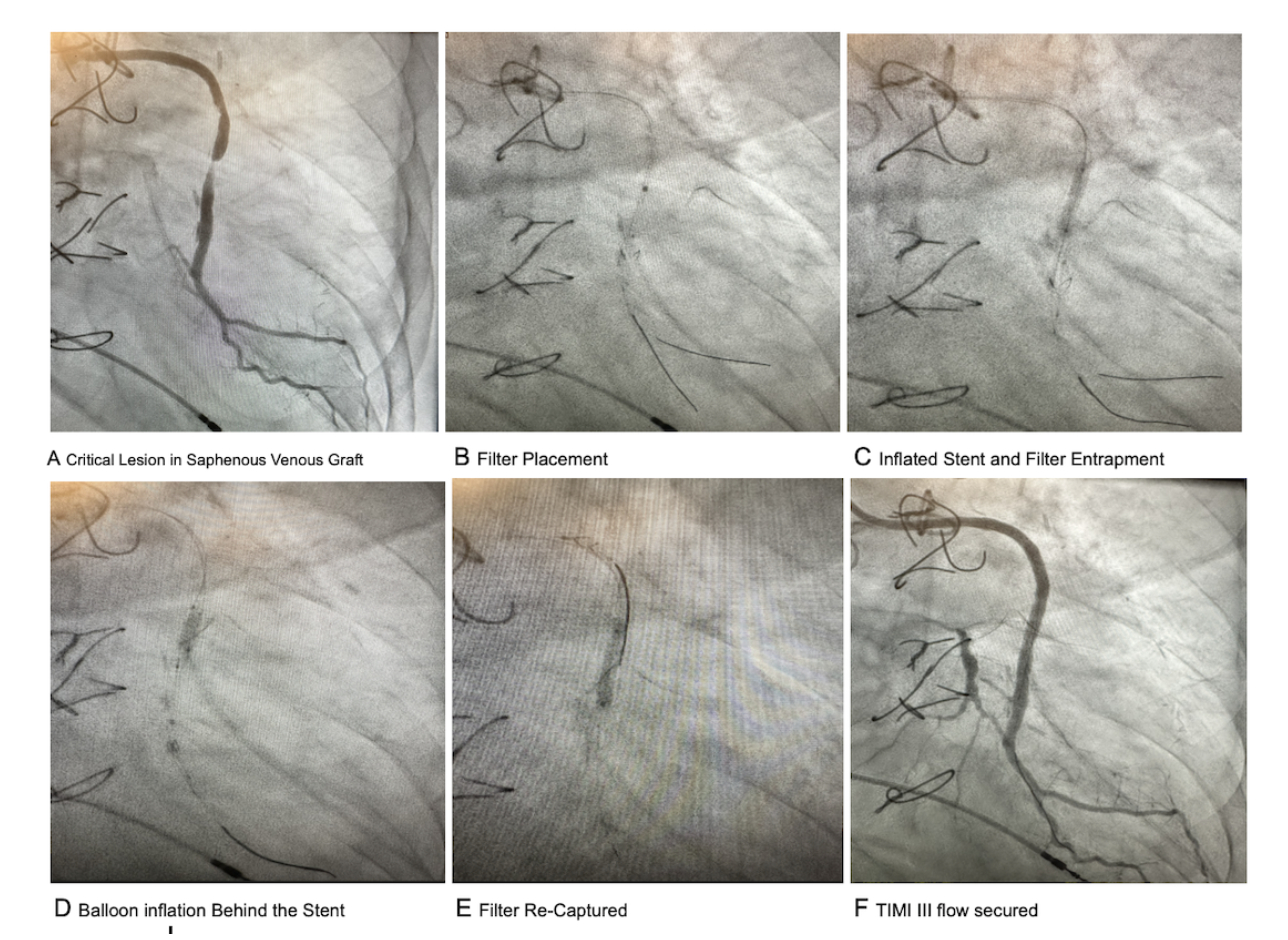

Removal of the Entrapped distal embolic protection system behind the stent frame during the percutaneous intervention of critically stenosed Saphenous venous graft. A Case Report.

The left coronary bypass catheter was used to cannulate the vein graft, supplying the obtuse marginal artery. Balanced middleweight universal wire (BMW) was used to cross the lesion. Given the critical nature of the lesion, it was pre-dilated using a 2 mm balloon. Bare wire and emboshield NAV6 (2.5-4.8mm) embolic protection was then used for distal protection. Due to hemodynamically intolerance, direct stenting was opted for, and a 3.5 x 16 mm synergy stent was deployed over the BMW wire with accidental entrapment of the bare wire and embossed filter protection system behind the stent frame.

We have then placed an un-inflated 2.5 mm balloon inside the stent frame over the BMW wire. A 1 mm sapphire balloon was advanced over the bare wire, and its distal tip was placed behind the proximal edge of the stent. It was then inflated at 8 atmospheres. Serial inflations behind the stent frame were done with slow advancement of the balloon, covering the entire length of the stent. The balloon was then upsized to 2 mm, and serial inflations were performed behind the stent frame. After creating enough lumen, the filter was pulled back and re-captured. The 2.5 mm balloon was then inflated inside the stent frame. The balloon was upsized to 3.5 mm for the good apposition of the stent frame. TIMI III flow was obtained without any complications.

Distal embolic protection with intravascular filters is often used during percutaneous intervention of saphenous venous grafts. Accidental entrapment of emboshield filter systems can occur behind the stent in emergent situations when buddy wire technique is used in the vein graft. Our technique describes removal of the entrapped filter in a safe manner keeping the stent frame in place without surgical intervention. A few similar cases have been reported in the literature with surgical removal of wire.